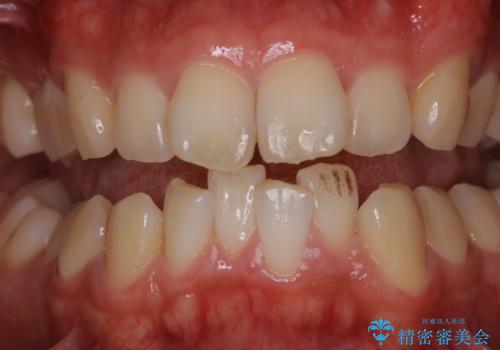

[エアフロー] スプレーの噴射によりしつこい色素沈着やプラークを除去

![[エアフロー] スプレーの噴射によりしつこい色素沈着やプラークを除去の症例 治療前](https://seimitsushinbi.jp/wp/wp-content/uploads/2021/11/IMG_9998-500x350.jpg?v=1636593297)